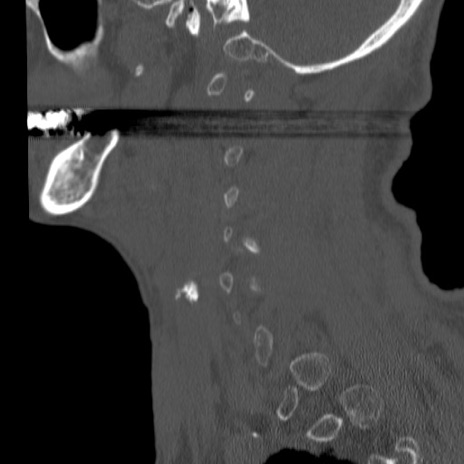

症例46 頚椎CT(矢状断像)

【症例】80歳代男性

【主訴】両側頚部〜上肢のしびれ

【現病歴】昨日、自宅内で転倒、その後より上記症状あり。意識障害なし。

【身体所見】両側上肢のallodynia(熱痛覚過敏)あり。MMTおよびDTRは正確な所見取れず。両上肢の挙上はなんとか可能。

異常所見と診断は?